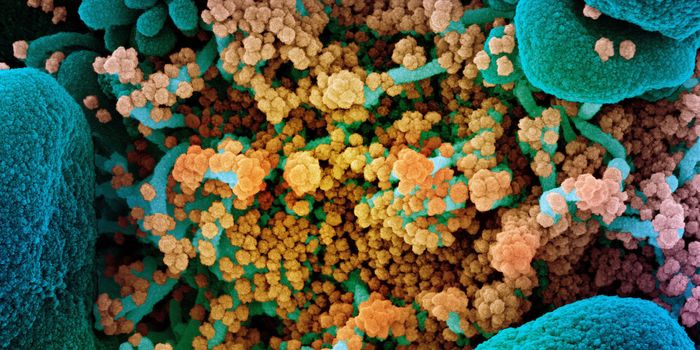

MAR 22, 2020MicrobiologyMore data is being gathered from an unfortunate and dramatic rise in the number of COVID-19 cases around the world.

APR 01, 2020MicrobiologyThere are a couple of different kinds of tests that researchers will be developing and clinicians will be using to disru ...

MAY 03, 2020Genetics & GenomicsThe origin of SARS-CoV-2, the pandemic virus that causes COVID-19, has become politicized as leaders seek to place blame ...

JUL 06, 2020MicrobiologyThe pandemic coronavirus has caused a wide range of different symptoms, and as time goes on, we may find that it can hav ...

JUL 05, 2020Cell & Molecular BiologyThe pandemic virus SARS-CoV-2 enters the body through the respiratory system to cause the illness COVID-19. But we know ...

JUN 29, 2020MicrobiologyVaccines that contain live attenuated viruses may be giving people some protection from serious cases of COVID-19 that i ...

FEB 22, 2021MicrobiologyReporting in Science, researchers have created an antiviral nasal spray that could help us get the COVID-19 pandemic und ...

SEP 01, 2021MicrobiologyIt's been generally assumed that people who get infected with SARS-COV-2 will develop antibodies to the virus, which cau ...